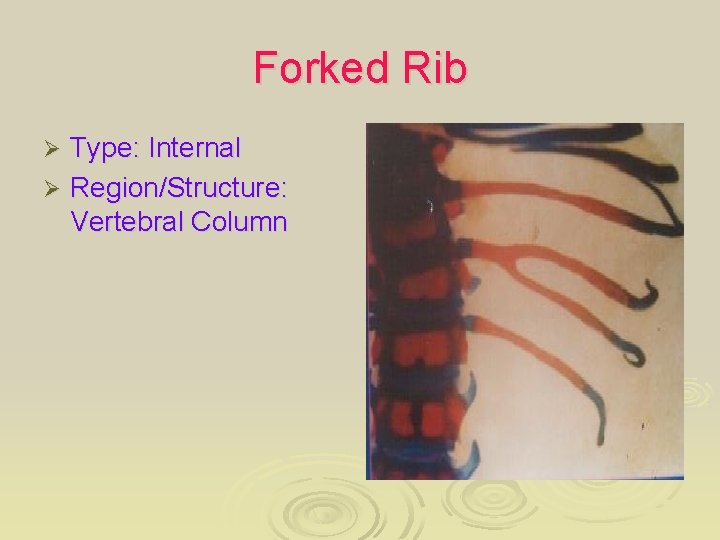

Forked Rib Type: Internal Ø Region/Structure: Vertebral Column Ø